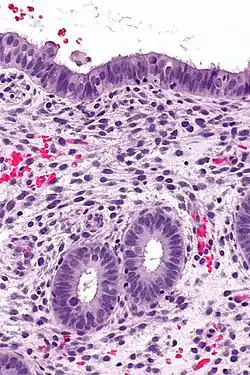

The endometrium consists of a single layer of columnar epithelium plus the stroma on which it rests. The stroma is a layer of connective tissue that varies in thickness according to hormonal influences. In the uterus, simple tubular glands reach from the endometrial surface through to the base of the stroma, which also carries a rich blood supply provided by the spiral arteries. In women of reproductive age, two layers of endometrium can be distinguished. These two layers occur only in the endometrium lining the cavity of the uterus, and not in the lining of the fallopian tubes.[4][5]

Endometrioid adenocarcinoma from biopsy. H&E stain.

Micrograph of decidualized endometrium due to exogenous progesterone. H&E stain.

Micrograph showing endometrial stromal condensation, a finding seen in menses.